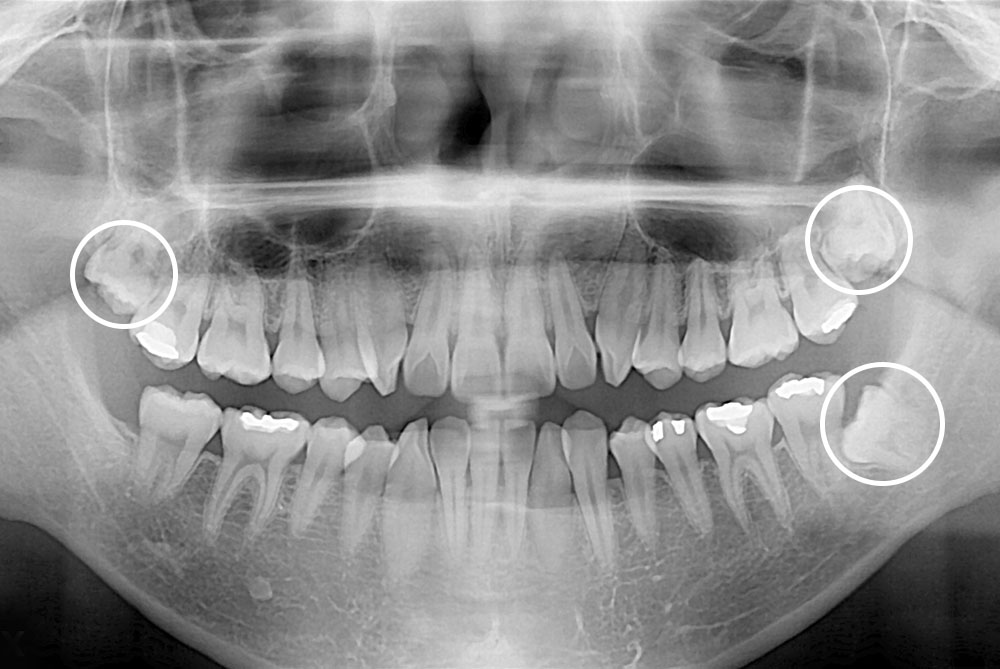

[사랑니] 매복 사랑니 발치

치료전 : 2018-10-04